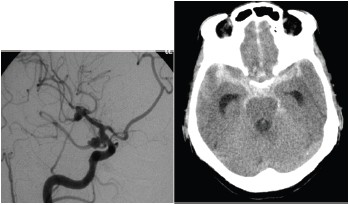

Considere uma paciente feminina, 59 anos, cefaleia inédita súbita de forte intensidade apresentando sonolência com pronto despertar, respondendo adequadamente aos comandos verbais com os seguintes exames de imagens.

É correto afirmar que se trata de: